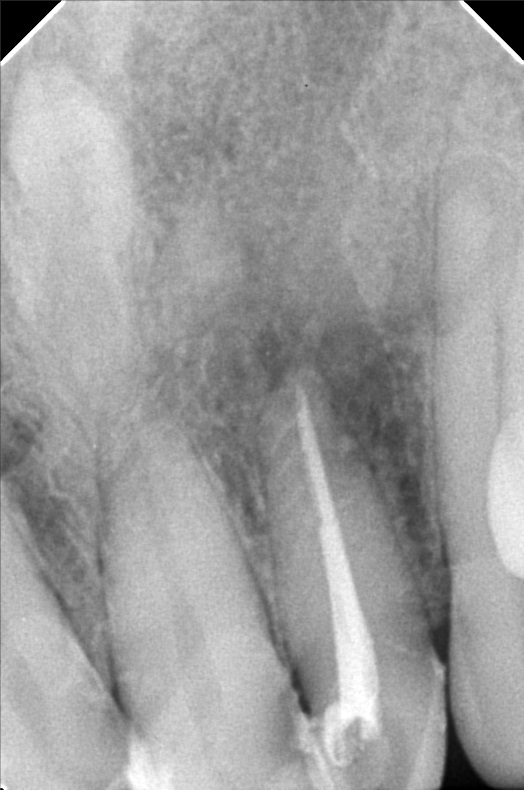

- 10/05/21 -0p/ Lc 11m/21M *22 subject for rct *11 distal repeat lc/ 21 repeat lc/ 12 lingual repeat lc 10/15/21- rct 22mm/ apical abcess laser done apexcal 10/22/21 - LC #12 mesial #11 Lc Distal #21 Distal LC #22 veneer #22 obturate- 22mm guttaflow 04/02/22- veneer due to spaces #41/42/43/31/32/ shade A3/ esthetica 08/25/2023- Cleaning veneer re-polish 11/12/22/21

- bonifacio3.jpg